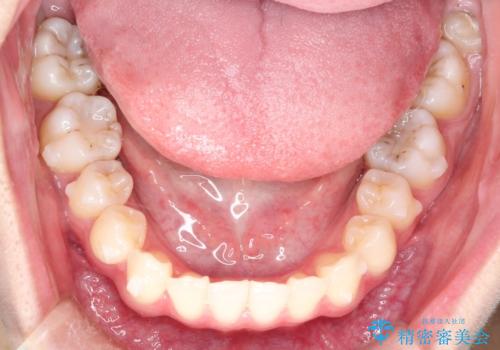

インビザラインによる非抜歯矯正 ガタガタな歯並びを整った歯並びへ

- 前歯のガタガタを主訴に来院されました。

抜歯矯正も考えられる状態でしたが、非抜歯矯正を希望されました。

使用時間を守っていただけたので、スムーズに治療を終わることができました。